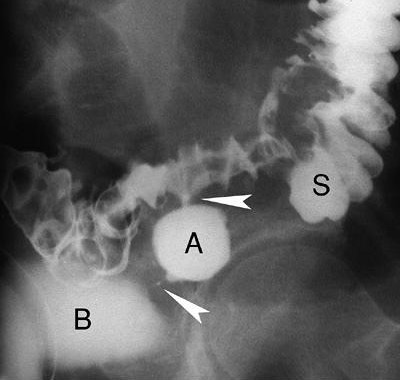

Viêm túi thừa thường có thủng và áp xe khu trú trong thành hoặc áp xe quanh đại tràng. Viêm túi thừa là biến chứng xảy ra trong 20% bệnh nhân có túi thừa. Biến chứng của viêm túi thừa gồm tắc ruột, chảy máu, viêm phúc mạc, và tạo thành đường rò hoặc đường xoang (sinus: các đường hầm không có lỗ mở ra ngoài hoặc vào tạng rỗng). Các đường xoang có thể tạo thành các ổ áp xe lớn ở trong khoang phúc mạc hoặc khoang sau phúc mạc. Các đường rò thường tới bàng quang (Hình 22), âm đạo, hoặc da, hoặc các cơ quan khác trong tiểu khung. Dấu hiệu xác nhận của viêm túi thừa khi chụp baryt bao gồm các túi thừa biến dạng, trào thuốc ra khỏi lòng đại tràng (đôi khi chạy song song với lòng đại tràng gọi là dấu hiệu đường đôi), hiệu ứng khối của áp xe (hẹp lòng đại tràng thuôn, nhẵn).

Hình 22. Hình áp xe túi thừa và rò đại tràng-bàng quang. Chụp cản quang đơn cho thấy baryt đọng trong áp xe túi thừa (A) và mờ bàng quang (B). Các cột baryt (đầu các mũi tên) vạch các đường rò kéo dài từ lòng đại tràng tới ổ áp xe và từ ổ áp xe tới bàng quang. Lòng đại tràng sigma (S) bị hẹp không đều do quá trình viêm.